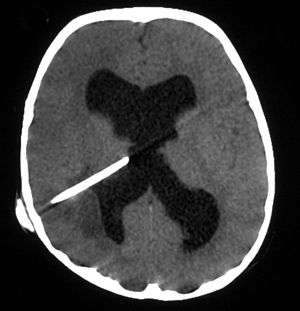

_--_showing_a_small_ring-enhancing_lesion_with_mild_surrounding_edema_adjacent_to_the_ventricular_catheter_and_ventricular_dilatation..jpg)

The diagnosis is established by a computed tomography (CT) (with contrast) examination. At the initial phase of the inflammation (which is referred to as cerebritis), the immature lesion does not have a capsule and it may be difficult to distinguish it from other space-occupying lesions or infarcts of the brain. Within 4–5 days the inflammation and the concomitant dead brain tissue are surrounded with a capsule, which gives the lesion the famous ring-enhancing lesion appearance on CT examination with contrast (since intravenously applied contrast material can not pass through the capsule, it is collected around the lesion and looks as a ring surrounding the relatively dark lesion). Lumbar puncture procedure, which is performed in many infectious disorders of the central nervous system is contraindicated in this condition (as it is in all space-occupying lesions of the brain) because removing a certain portion of the cerebrospinal fluid may alter the concrete intracranial pressure balances and causes the brain tissue to move across structures within the skull (brain herniation).